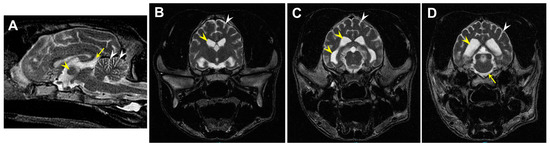

3.1. Disease Pathology